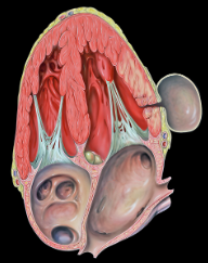

Entre as principais características, observa-se que cerca de um terço dos casos é diagnosticado nas primeiras duas semanas, tendo tempo médio de diagnóstico em torno de 50 dias. A principal etiologia é o infarto agudo do miocárdio, embora a lesão também possa ocorrer secundariamente a trauma torácico penetrante, endocardite infecciosa ou no pós-operatório de cirurgia cardíaca. Do ponto de vista anatomopatológico, trata-se de uma ruptura miocárdica contida por tecido fibroso, pericárdio e coágulos, o que explica sua apresentação subaguda, como podemos observar na tabela 1.

As localizações mais frequentemente acometidas são a parede inferior ou lateral, apresentando mortalidade inferior a 10%, porém com risco significativo de ruptura, estimado entre 30% e 45%.